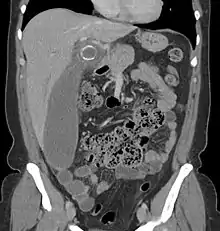

A CT scan demonstrating acute appendicitis (note the appendix has a diameter of 17.1 mm and there is surrounding fat stranding)

Where it is readily available, computed tomography (CT) has become frequently used, especially in people whose diagnosis is not obvious on history and physical examination. Although some concerns about interpretation are identified, a 2019 Cochrane review found that sensitivity and specificity of CT for the diagnosis of acute appendicitis in adults was high.[59] Concerns about radiation tend to limit use of CT in pregnant women and children, especially with the increasingly widespread usage of MRI.[60][61]

The accurate diagnosis of appendicitis is multi-tiered, with the size of the appendix having the strongest positive predictive value, while indirect features can either increase or decrease sensitivity and specificity. A size of over 6 mm is both 95% sensitive and specific for appendicitis.[62]

However, because the appendix can be filled with fecal material, causing intraluminal distention, this criterion has shown limited utility in more recent meta-analyses.[63] This is as opposed to ultrasound, in which the wall of the appendix can be more easily distinguished from intraluminal feces. In such scenarios, ancillary features such as increased wall enhancement as compared to adjacent bowel and inflammation of the surrounding fat, or fat stranding, can be supportive of the diagnosis. However, their absence does not preclude it. In severe cases with perforation, an adjacent phlegmon or abscess can be seen. Dense fluid layering in the pelvis can also result, related to either pus or enteric spillage. When patients are thin or younger, the relative absence of fat can make the appendix and surrounding fat stranding difficult to see.[63]